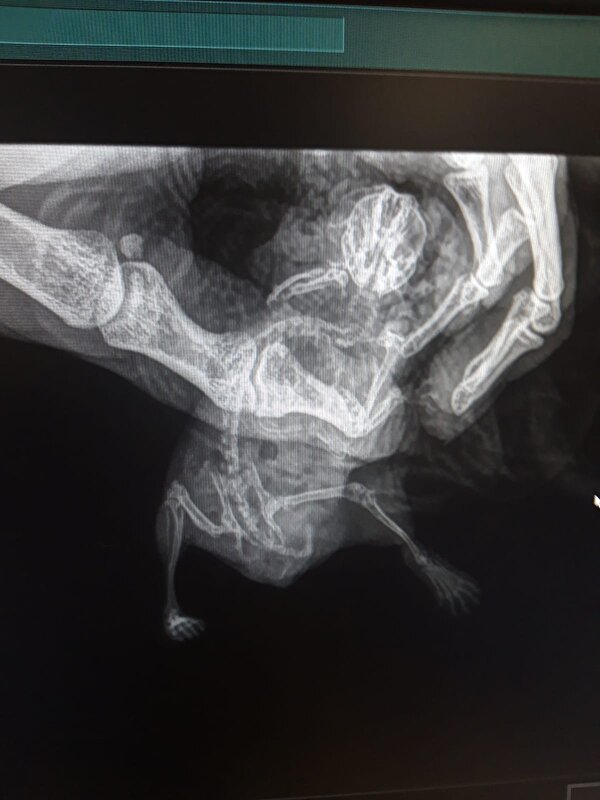

paardje2013 schreef:Ik ben bang dat de dierenarts hier niet zo veel hamsters op het spreekuur krijgen dus er is vast ook niet veel ervaring mee. Maar kan een hamster met 3 voetjes leven? Of is het niet fijn voor dit diertje

Er zijn ook jonge hamstertjes die bij de geboorte al een pootje missen als mama wat onhandig is. Er zijn ook hamsters die om welke reden dan ook later een pootje moeten amputeren. Het gebeurd helaas (en gelukkig niet alleen maar door ladders ..